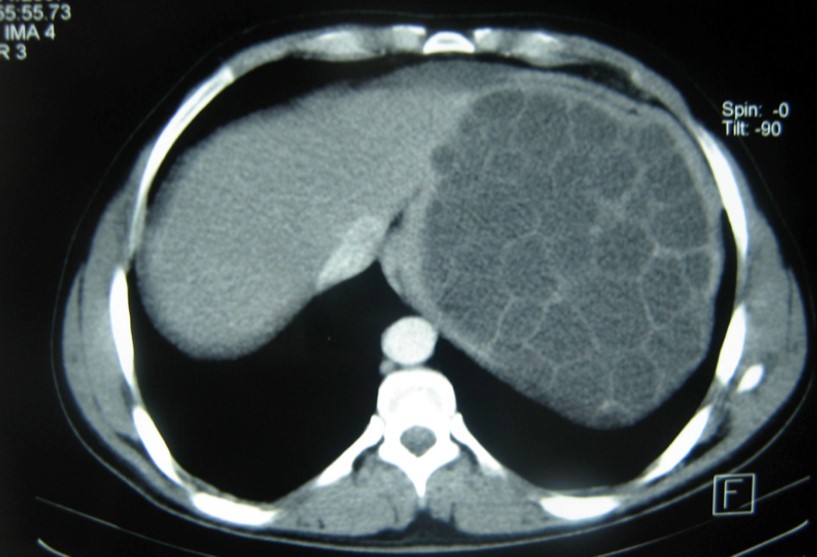

A 17-year-old young man admitted to our department with the complaint of abdominal pain localized in the left upper quadrant for the last 3 months. His physical examination revealed a splenomegaly. Immunoblot assay for Echinococcus was positive. His laboratory tests showed normal results of the serum and urine examinations, No eosinophilia was found. Chest X-ray revealed no pathological signs. An abdominal ultrasonography showed a 20 cm multivesicular cystic mass of spleen (figure 1). Contrast enhanced CT scans detected a huge single 20×16×18cm cystic mass located in the spleen. It had well-defined borders and contained multiple, round, daughter cysts in the periphery of the lesion with calcification (Figure 2, Figure 3, Figure 4). The patient underwent a laparotomy. A large splenic cystic mass was identified, attached to diaphragm, and tail of the pancreas (figure 5). The abdomen was packed with 10% hypertonic saline soaked pads in order to protect peritoneal soilage. A partial cystectomy without splenectomy was performed. Histologic examination of the specimen resection showed an echinococcal organism residing within the hydatid cyst . The patient was discharged after 4 postoperative days. 600 mg per a day of Albendazole therapy was instaured postoperatively and continued for 6 months. Two years after surgery the patient is well with disease free.

Figure 2.CT showing a huge single 20×16×18cm cystic mass located in the spleen

Figure 3.CT showing a huge single 20×16×18cm cystic mass located in the spleen